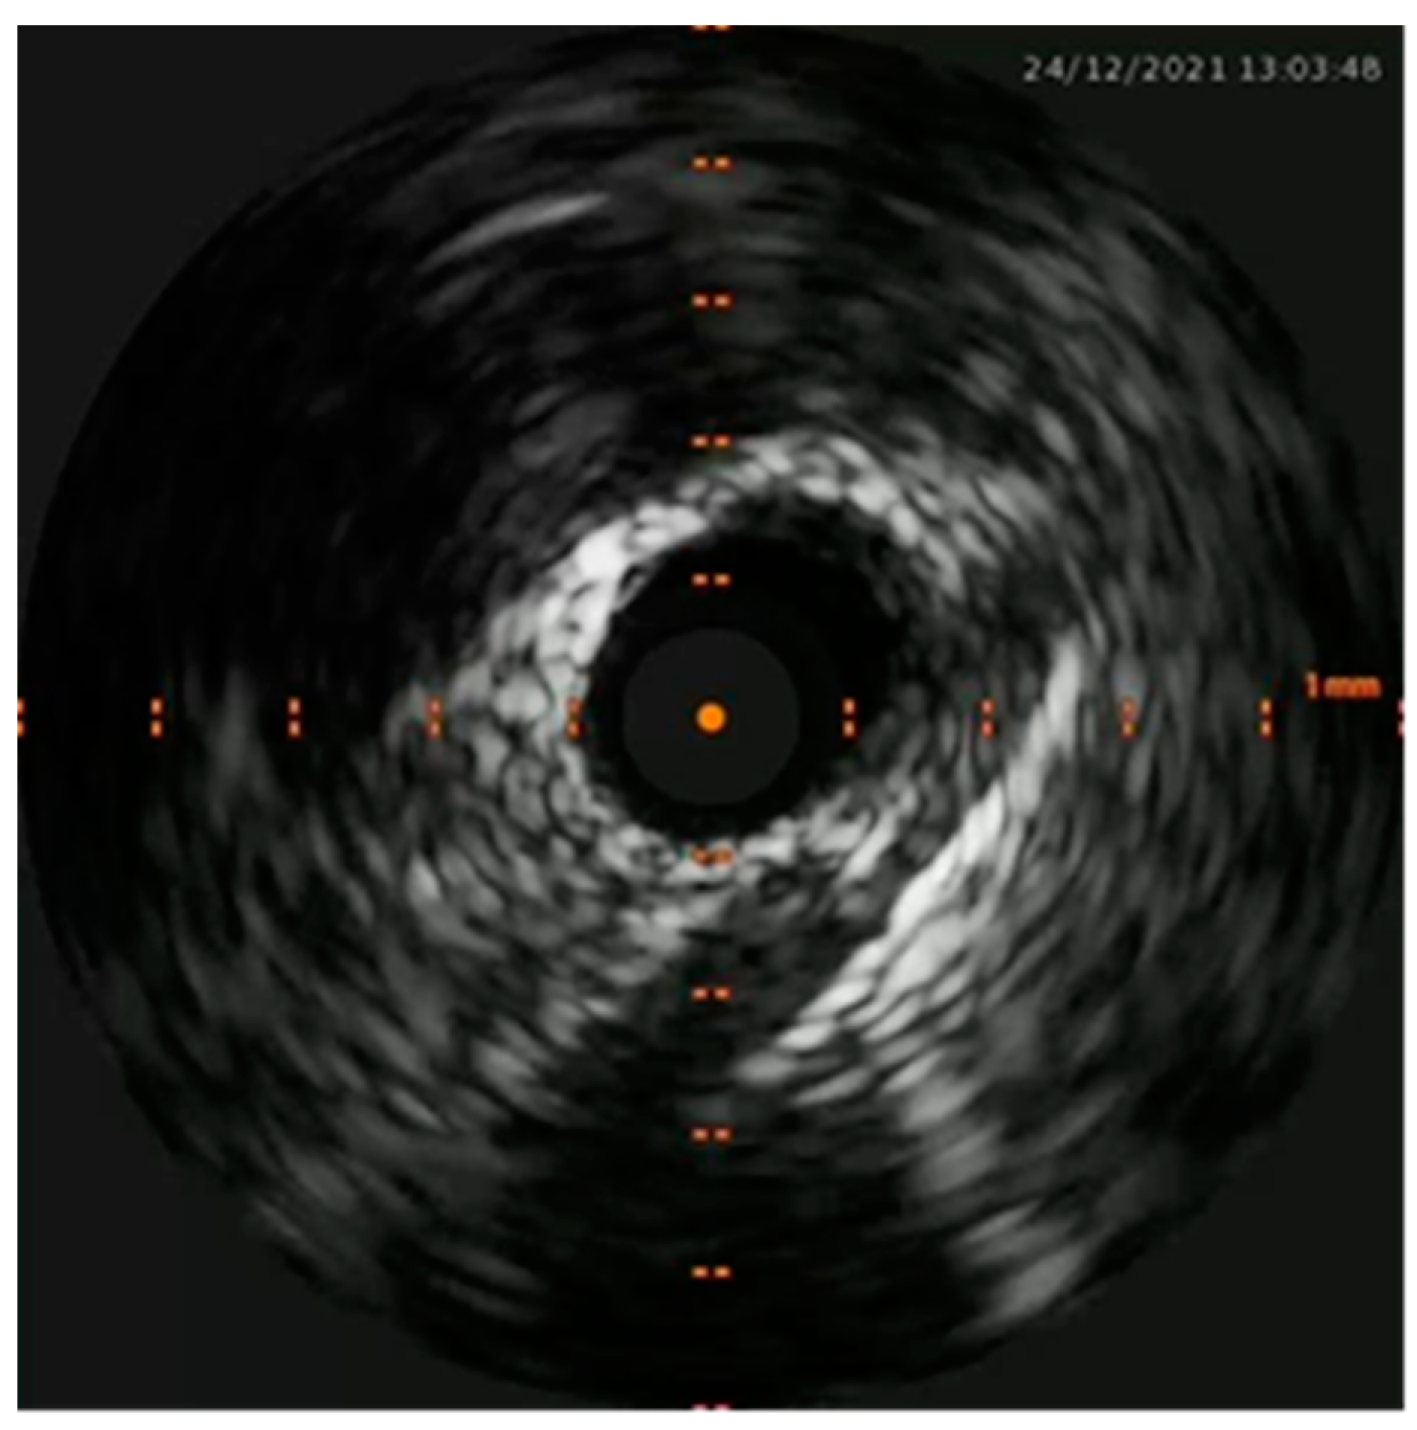

Percutaneous coronary intervention was therefore considered appropriate and a purposely undersized EBU 3.0 6F was selected. A safety wire, Runthrough floppy, was immediately placed on the patent left circumflex artery whilst after failing wiring on the left anterior descending with a Balance Middleweight wire a Sion wire was advanced up to the apical LAD. An IVUS run confirmed distal true lumen wire position showing a short subintimal track without compromise of any major side branch. (Figure 4, Figure 5, Figure 6 and Figure 7)

Figure 6. IVUS showing distal true lumen.

Figure 7. Short subintimal track with compressed true.